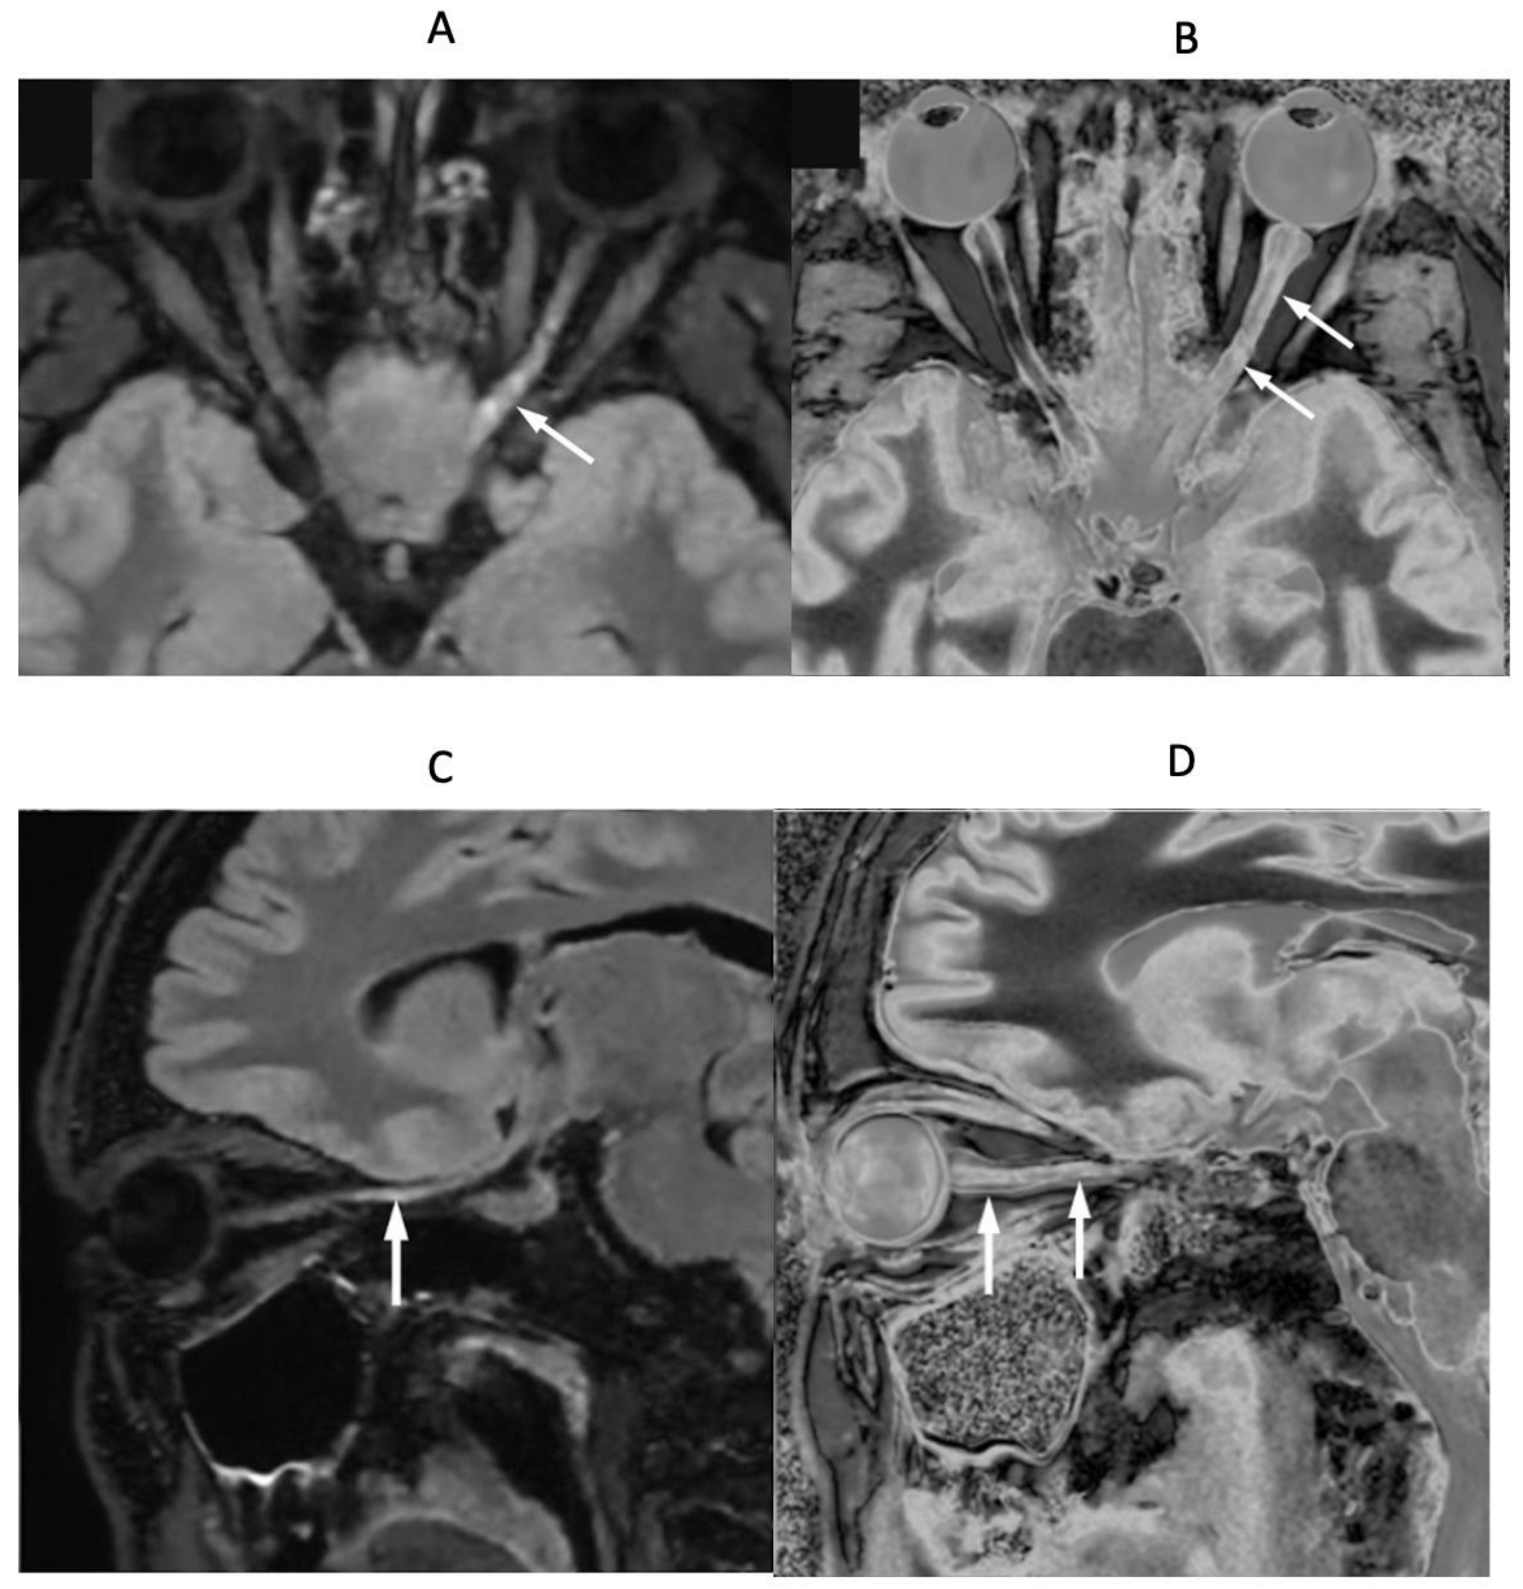

4. Illustrative Cases